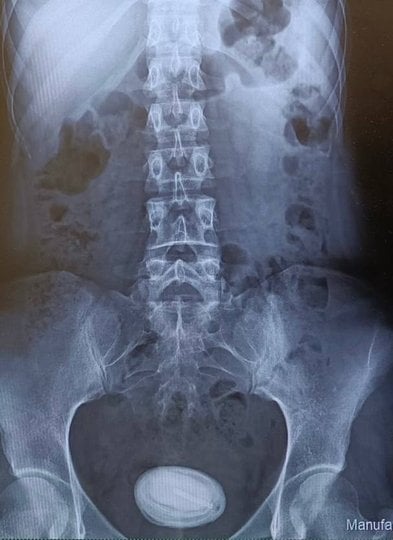

До медиків лікарні швидкої допомоги звернулася 25-річна тернополянка. Жінка скаржилася на хронічний цистит. З кожним днем їй ставало все гірше, а традиційне лікування не допомагало. Лікар-уролог призначив детальне обстеження для встановлення причин такої патології. Під час УЗД, у сечовому міхурі, було виявлено нетиповий великий утвір розміром 5,5 на 4,5 сантиметри.

«Лікарі-урологи призначили додаткові обстеження, зокрема рентген та цистоскопію. Завдяки цим аналізам остаточно підтвердилося, що "камінь" у сечовому міхурі жінки насправді був протизаплідною спіраллю, яка потрапила в порожнину органу і вкрилась шаром камʼяних відкладень», – повідомили в Тернопільській міській комунальній лікарні швидкої допомоги.